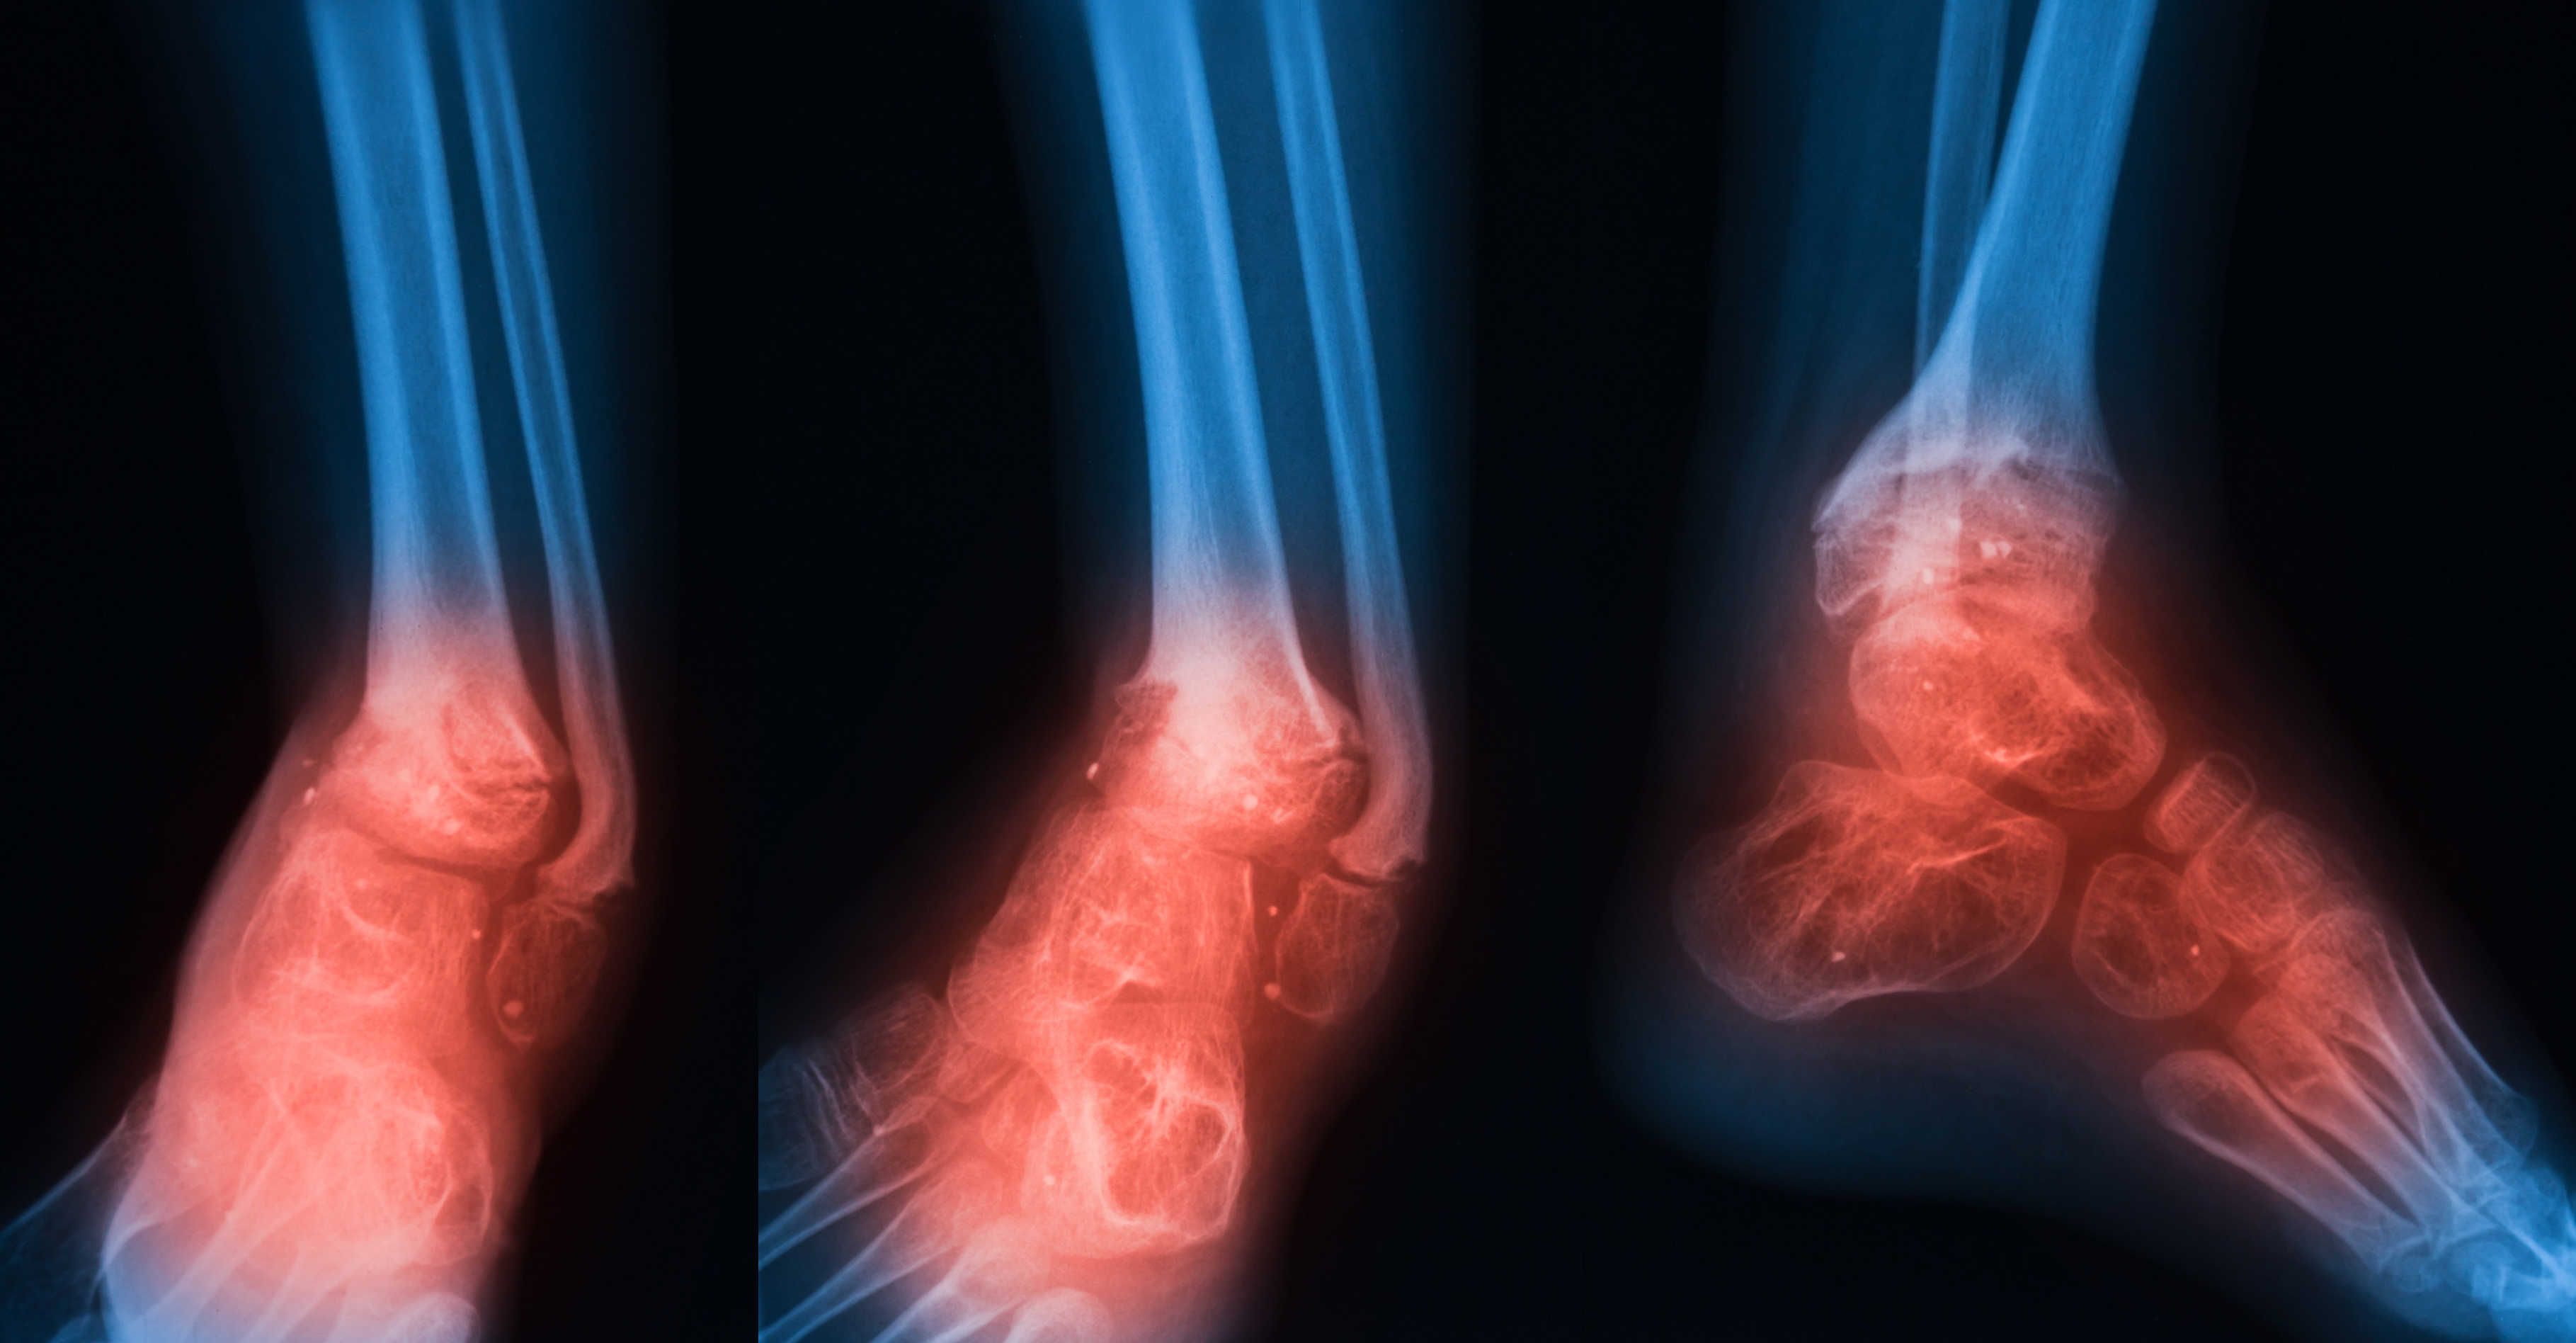

Osteomielitis adalah jangkitan tulang yang jarang berlaku tetapi serius. Jangkitan tulang boleh menjadi akut atau kronik. Jika pesakit tidak mempunyai rawatan yang betul, tulang tertentu boleh rosak secara kekal. Ia disebabkan oleh bakteria atau kulat yang menyerang tulang. Pada kanak-kanak, tempat yang paling popular di mana jangkitan tulang berlaku adalah pada tulang panjang lengan dan kaki. Sebaliknya, jangkitan kelihatan pada pinggul, tulang belakang, dan kaki.